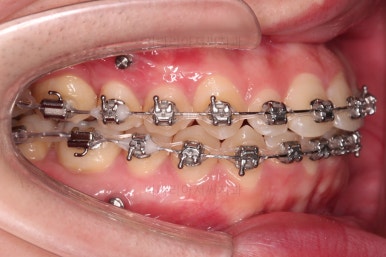

우선 브라켓을 부착했고요.

이번에 환자분이 선택하신 장치는 엠파워 메탈이라고 하는 자가결찰 금속장치인데요.

메탈이라고 다 구형의 장치는 아니고 "자가결찰"인지 여부가 굉장히 중요해요.

미니스크류가 식립되었고요.

결손치아도 오른쪽, 부정교합도 오른쪽이어서 오른쪽 위아래 각 1개씩 식립이 되었어요.

물론 윗니는 앞으로 당기는 용도, 아랫니는 뒤로 미는 용도였습니다.